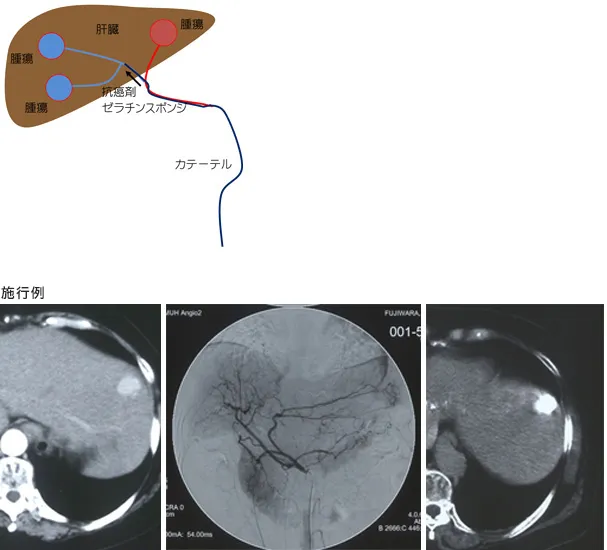

肝動脈化学塞栓療法(TACE)

肝動脈化学塞栓療法(TACE)とは肝がんへ血液を送っている動脈から抗癌剤を注入後その動脈を塞ぐ治療法です。

肝臓は、肝動脈と門脈という2つの血管から血液の供給を受けていますが、肝がんは、肝動脈からの血流が大部分を占めています。一方、正常の肝臓はほとんど門脈から血液を受けます。

そのため肝動脈に抗癌剤を注入し、その動脈を塞げば、ほぼ腫瘍のみを壊死に導くことができ、正常な細胞は門脈からの血液によりほとんど障害を受けずに済みます。

具体的には、カテーテルという細い管を、局所麻酔後、大腿部のつけ根にある大腿動脈あるいは腕の動脈から挿入して、肝動脈までカテーテルを進め、油性造影剤と抗がん剤の混合液を注入します。抗がん剤には、ドキソルビシン(アドリアマイシン)やエピルビシン、マイトマイシンC、シスプラチン、ミリプラチンなどを使います。その後、塞栓物質として1mm角前後の細かいゼラチンスポンジを注入して動脈を閉塞します。

左:治療前CT動脈相

中:血管造影

右:治療後単純CT(肝がんに集積した抗癌剤は白く見える)

治療前CTで認められた肝がんは血管造影で黒く染まり、この動脈より肝動脈塞栓術を施行したところ、治療後CTで肝がんに抗癌剤が100%集積しているのを確認された。